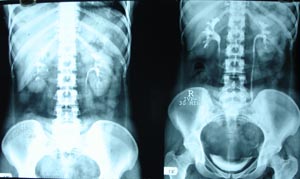

Intravenous pyelography

It reveals a staghorn calculas on right side with absent nephrogram on right side. Left kidney shows compensatory hypertrophy.